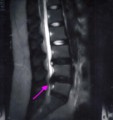

2009年02月06日 13:48

今日2ヶ月半ぶりのMRIを撮ってきた。 結論から言うと・・・ よくなってなかった。 むしろ、悪い方向に・・・ 全体的に調子はよく・・・期待して病院へ行っただけに ショックだった。 ショックで今後... 続きを読む